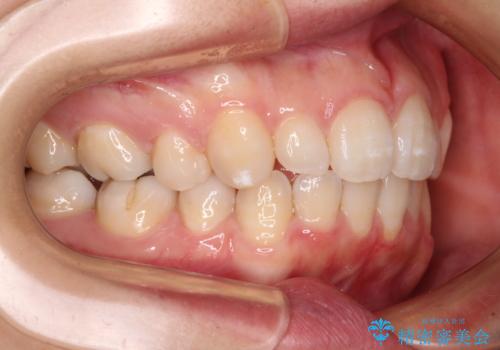

- 30代女性

- 下顎前歯を中心に、以前行った矯正治療の後戻りが気になるとのことで来院された患者様です。

後戻りは軽度であったため、インビザライン・ライトにて治療を行うこととしました。

治療途中で出産をされたため、通院が困難となりましたが、インビザライン・ライトでの治療可能期限である2年以内に無事に治療を終えることができました。